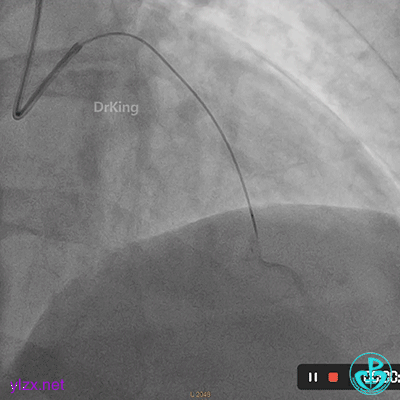

首选开通右冠脉,导丝到达闭塞段远端,球囊扩张后,可见大量血栓,抽吸导管反复抽吸出大量血栓。冠脉内推注尿激酶原20mg,复查造影提示右冠脉远端显影,调整导丝至远段。

球囊再次扩张闭塞段,并对后降支及左室后支开口行对吻球囊扩张,复查造影示血流3级,无夹层行成,右冠脉远段仍可见血栓影。